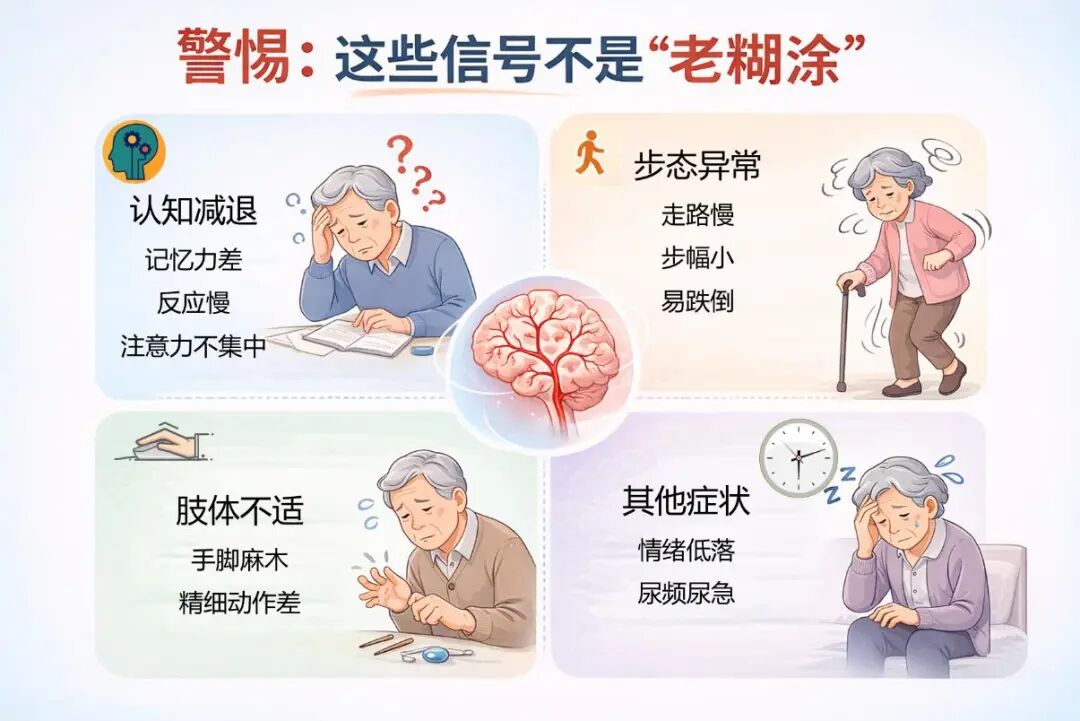

警惕:这些信号不是“老糊涂”

•认知减退:记忆力差、反应慢、注意力不集中,做事丢三落四。

•步态异常:走路慢、步幅小、身子不稳,头晕频发,跌倒风险高。

•肢体不适:手脚麻木僵硬、无力,扣纽扣、拿筷子等精细动作变差。

•其他表现:莫名情绪低落、睡眠差、尿频尿急。